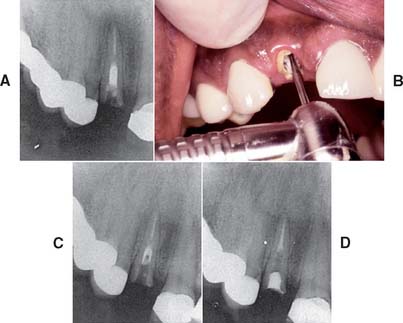

On occasion, an existing post and core must be removed (e.g., for re-treatment of a failed root canal filling). Patients must understand in advance that post removal is a risky process and occasionally results in radicular fracture. If sufficient length of post is exposed coronally, the post can be retrieved with thin-beaked forceps. Vibrating the post first with an ultrasonic scaler weakens brittle cement and facilitates removal. A thin scaler tip or special post removal tip is recommended (Fig. 12-47). Although histologic examination with animal models reveals no harmful effect in the periodontal tissues,86 ultrasonic removal is slower than other methods and may result in an increased number of canal and intradentin cracks.87 Alternatively, a post puller can be used.88 This device consists of a vise to grip the post and legs that bear on the root face. A screw activates the vise and extracts the post.

Fig. 12-47 Post removal by ultrasonic device. A, Preoperative radiograph of the left maxillary first premolar with a parallel-sided threaded post that had to be removed for endodontic retreatment. B, After the coronal portion of the post has been well isolated, the tip of the ultrasonic device is placed against it, and energy is applied to disrupt the cement interface. Note the suction tip, which removes water spray used with the ultrasonic handpiece. C, After a time, the post becomes loose within the canal and can be retrieved by forceps. D, Radiograph of the premolar after post removal.

(Courtesy of Dr. L. L. Lazare.)